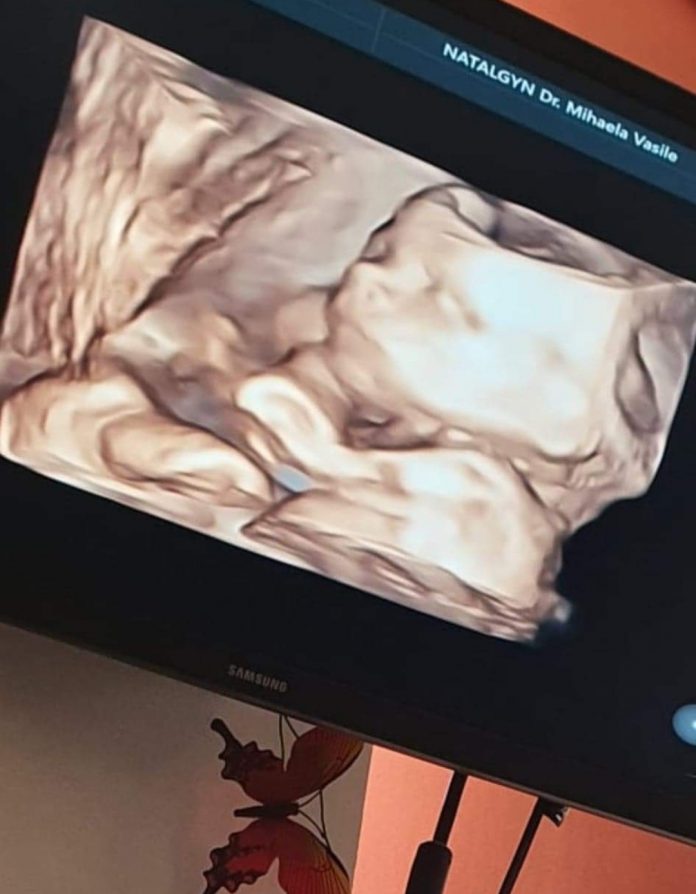

Familia Sechi din Rovinari este acum la Spitalul Județean de Urgență  Nr 1 Craiova, așteptând, ca echipa Secției Ginecologie să intervină și să scoată din pacienta de la Gorj fătul mort. Gravida a fost internată la această unitate medicală, de vineri, prin UPU, dar au trecut in jur de 30 de ore și medicii nu au pus încă femeia însărcinată, în pericol de septicemie, pe masa de operație, motivând că vor să îi provoace o naștere normală, luni dimineață. Cumplit este că medicul ginecolog care a urmărit sarcina în privat, Dr.Vasile Mihaela din Craiova, intenționa să interneze gravida de la Gorj abia luni în spitalul din Bănie, trimițând vineri familia Sechi înapoi acasă, dupa ce le-a dat vestea că sarcina, ajunsă la 5 luni și trei săptămâni, s-a oprit din evoluție.

,,Doctorita a liniștit-o pe soție mea spunându-i că fătul este mai leneș și recomandându-i să îl mai miște de burtă. Chiar a mișcat-o și doctorița cu un aparat. I-a recomandat apoi să își facă trombofilia, cu mențiunea că la venirea rezultatelor, în 10-11 zile, soția să revină la cabinet pentru a vedea această analiză. Inima copilului încă bătea, deoarece i-a făcut soției ecograf”, a menționat soțul Florentinei Sechi.